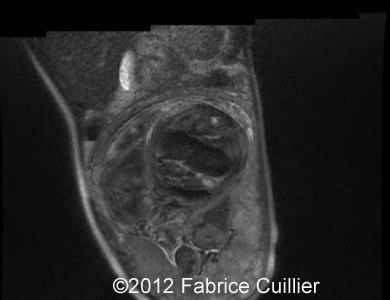

Image 8, 9: Abdominal fetal MRI  showed isolated intestinal dilatation with meconium inside.

9B

9A